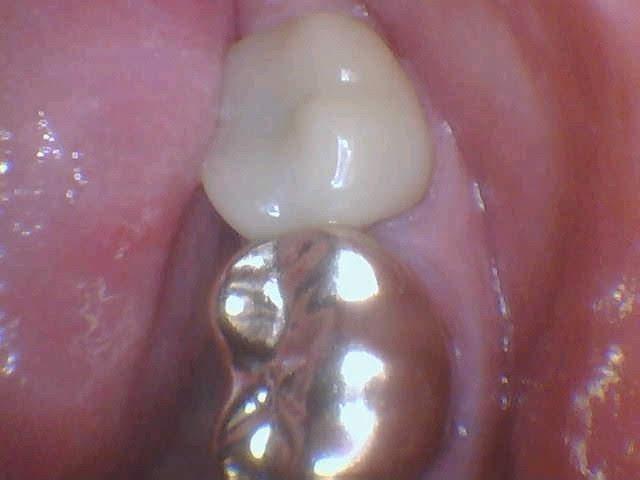

Same Day Crown

A same day crown completed to restore a cracked molar with recurrent decay.

Before